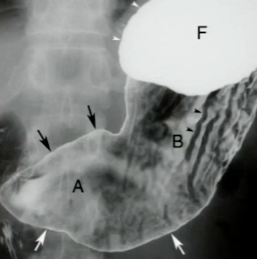

What is your diagnosis in this patient who presented with heart burn?

Sliding hiatal hernia. Note that the mucosal ring is > 2 cm superior to the diaphragm.